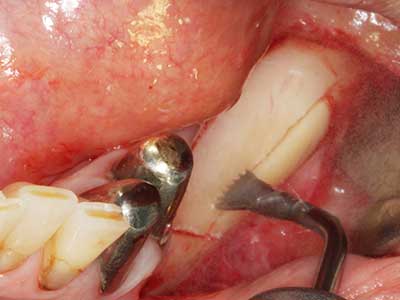

Abb. 20: Der entnommene Knochendeckel wird readaptiert und durch eine Osteosyntheseschraube (KLS Martin, Tuttlingen) fixiert.